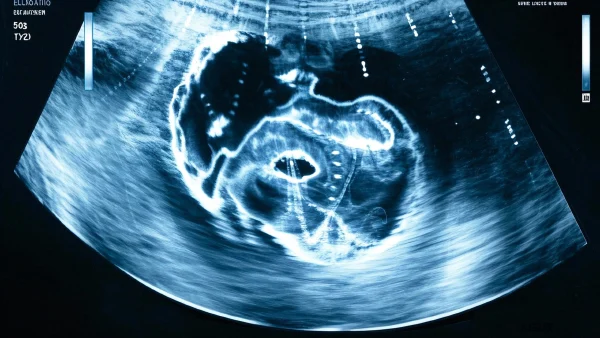

如果你见过B超检查,就知道那种在肚皮上晃来晃去的小探头,其实能把身体内部的结构“画”出来。简单来讲,超声利用高频声波穿过皮肤,然后在电脑屏幕上呈现胆囊及周围的图像。医生能通过胆囊的形态、壁厚以及周围是否有液体变化,判断是否有炎症发生。

超声检查不仅无痛无创,还能“动态”观察胆囊随呼吸轻微变化。这种方式在诊断胆囊炎方面非常实用,帮助医生筛查病变,也让患者少了很多顾虑。